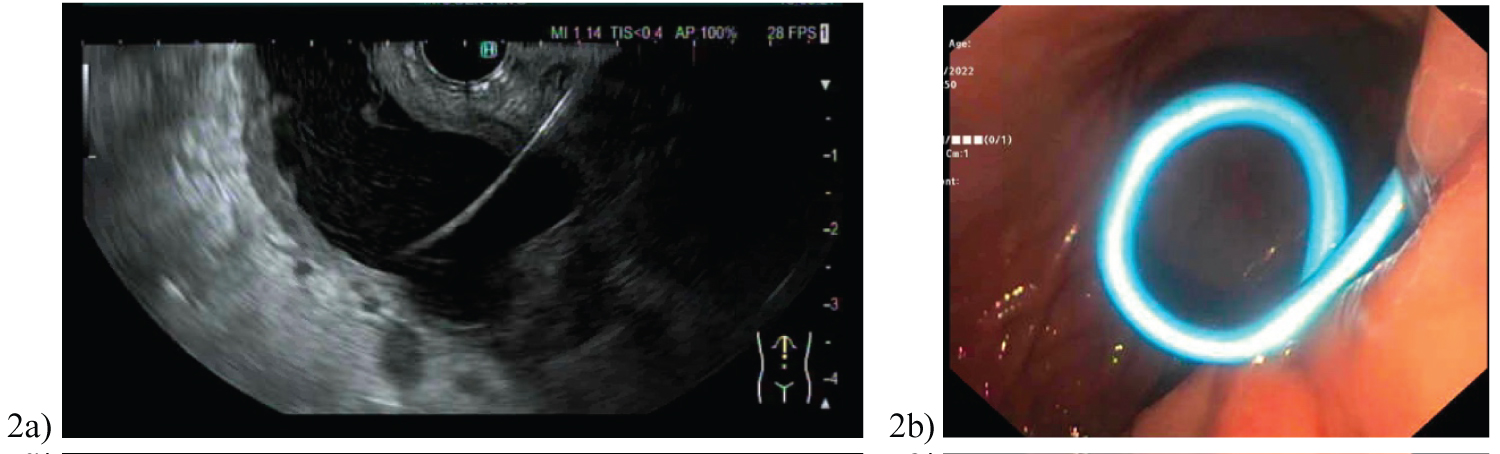

2 patients required repeat EUS, with Case 6 undergoing a further 2 transmural drainages on day 19 and 34 post injury. This pseudocyst likely recurred as initial transmural drainage day 12 post injuries, was via cystoenterostomy. Post initial cystogastrostomy, the patient developed worsening abdominal pain and fevers. MRI pancreas demonstrated an irregular Y-shape like gas-containing pseudocyst (38 × 40 × 49 mm) with extension into left upper quadrant (33 × 41 × 70 mm) and gastrohepatic ligament (21 × 21 × 18 mm) (Figure 5). On second EUS cystogastrostomy, pus was identified emanating from the 2 appropriately sited stents on the lesser curvature of the stomach. Stent dilatation was performed up to 10 mm, and a third double pigtail stent inserted to improve drainage.